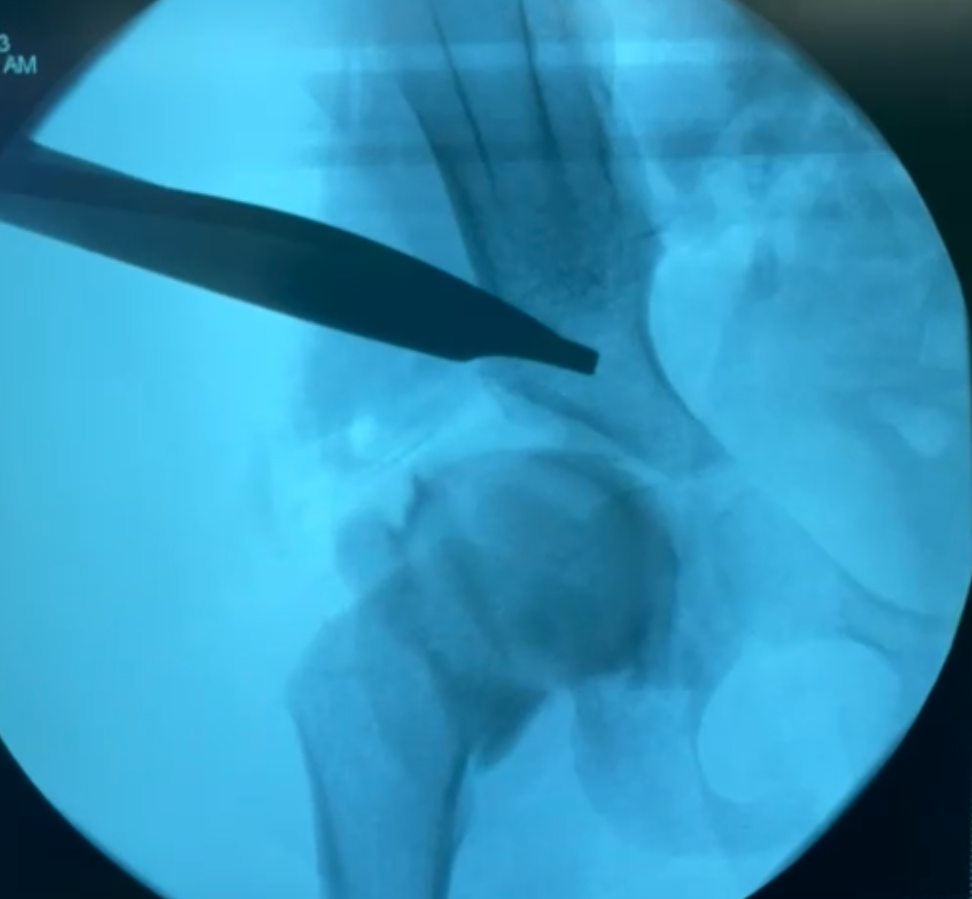

Data on the patient’s characteristics were prospectively collected from the patient’s electronic records and were directly entered into the database upon clinical presentation. This included information about the injury, treatment, complications, and mortality. Radiographs were also retrieved from the electronic patient records. Two trauma surgeons with more than 5 years of experience in pelvic ring injury surgery assessed the radiographic images (plain anteroposterior, inlet and outlet radiographs and CT scans) of all patients. Pelvic ring injuries were classified according to the Young-Burgess classification [11].

During the five years of the study, 128 patients with lateral compression pelvic injuries were treated in a level 1 trauma center. Of these patients, 97 were eligible to participate, as shown in Fig. 1. Of the patients who were included, the mean age was 55 (SD = 20) and 53% (n = 51) were female. Information regarding the injuries and injury mechanisms can be found in Table 1. Regarding treatment, most patients, 74 (76%), were treated conservatively. Conservative treatment consisted of a 6-week limited weight-bearing (20 kg) period with wheelchairs or crutches, followed by weight-bearing as tolerated.

Twenty-three patients (24%) underwent operative fixation. Of these, 11 patients (11%) were treated with only anterior pelvic ring fixation (10 plate osteosynthesis and one anterior screw fixation of the pubic rami), 8 patients (8%) with only posterior pelvic ring fixation (three patients with one sacroiliac screw, two patients with two sacroiliac screws, one patient with one trans-sacral screw, one patient with two sacroiliac plates and one sacroiliac screw and one patient with lumbopelvic stabilization), and 4 patients (4%) underwent both anterior and posterior pelvic ring fixation (all four patients had an anterior plate osteosynthesis and three patients had one additional sacroiliac screw and one patient had two additional sacroiliac screws). Furthermore, three patients (3%) were treated with an external fixator. The average time between admission and operation was 4 (SD = 3) days. The length of the hospital admission was an average of 10 (SD = 9) days. Following the admission, 33 (34%) were discharged to a care facility and 64 (66%) were able to go home. The number of patients with missing data at each follow-up moment ranged from 7 to 10, with different patients contributing to the missing data at each time point. These gaps were due to factors such as patients missing their follow-up appointment or surgeons not recording the data.